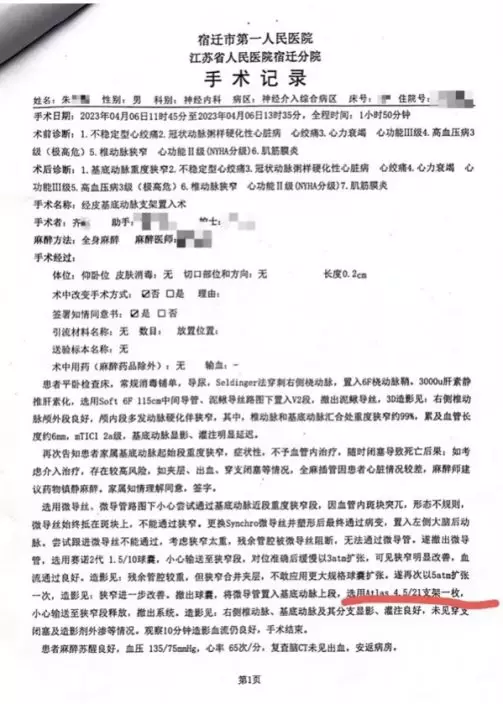

院方手術記錄報稱在向管內釋放支架,手術成功。

病程記錄多次提到向管狹窄情況改善。

當時醫生告知家屬,如果不予血管內介入治療,患者隨時可能因動脈閉塞導致死亡。經家屬簽字同意,4月6日,齊某再次作為主刀醫生,對朱老翁進行經皮基底動脈支架植入術,術後告知家屬手術成功。手術記錄均顯示,朱老翁安裝了一枚進口Neuroform Atlas 4.5/21支架,病程記錄也多次提到「血管狹窄明顯改善」。朱老翁4月10日「康復」出院,家屬結清了住院醫療費用,合計12萬餘元,部分自費。收據顯示,其中顱內支持導管收費1.88萬,神經導絲4275元,而Neuroform Atlas進口顱內支架為4.7萬元。

朱老翁「手術成功」出院,住院費約12萬元,部分自費。